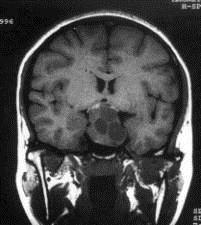

问题 病历摘要:??患者男性,35岁。性功能减退2年,视力下降6月。既往体健。体检:神清,皮肤细腻,毛发稀疏。视力左眼0.3,右眼0.5,双瞳等大等圆,直径3.5mm,对光反射稍迟钝,双颞侧偏盲,双眼底视神经乳头原发性萎缩,余神经系统未见异常。 垂体腺瘤目前主要治疗方法有哪些?